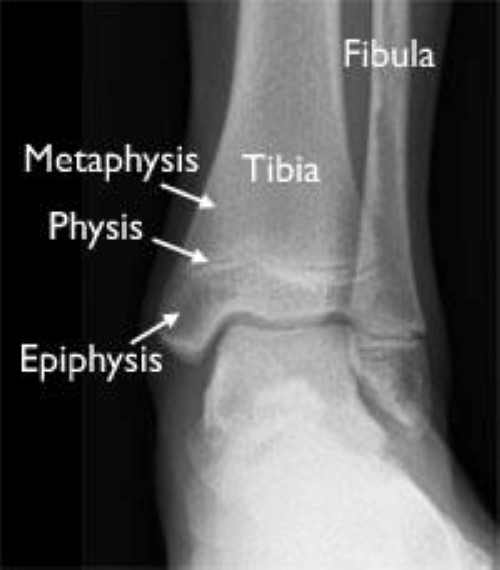

Hair line fracture is a common sports injury especially of the weight bearing bones such as tibia and metatarsals. 10 days later now it is discovered that there is hairline fracture in the foot.

The most common are metatarsal stress fractures (including 2nd, 4th & 5th), navicular stress fractures (aka.

The amount of time it takes for a stress fracture in a foot to heal depends on severity and how you're treating it. Having suffered hairline fractures in his foot while playing with one of his dogs, biden will likely require a walking boot for several weeks. Foot stress fractures are often caused by overuse or repetitive activities. A child bone fracture or a pediatric fracture is a medical condition in which a bone of a child (a person younger than the age of 18) is cracked or broken. Hairline, or stress fractures, are especially common in the foot bones. About 15% of all injuries in children are fracture injuries. A foot fracture can also happen during an accident or because of a medical condition, such as arthritis, that weakens the bones. A stress fracture or hairline fracture is not as immediately obvious as other types of breaks, but there are some symptoms that can be observed. This growth potential allows children's bones to remodel, or naturally correct some or all of the children have soft areas of cartilage at the ends of their bones, called growth plates, where growth takes place. Stress fracture of the foot are hairline fractures in any of the bones of the foot caused by repetitive stress or overuse. Treatment depends on the age, fracture pattern, and weight of the patient. Diabetic foot care | diabetes podiatry. My child fell down from monkey bar while playing but the doctor/radiologist failed to find fracture. It will depend where the broken bone is and the stability of the hairline fracture. While both of them are avid soccer players, they did not. The most common are metatarsal stress fractures (including 2nd, 4th & 5th), navicular stress fractures (aka. Hairline fractures are small cracks in a bone that occur after stress is placed on the lower leg.